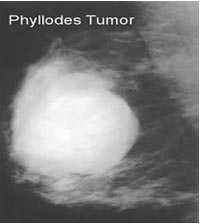

- Chụp nhũ ảnh: tương tự bướu sợi tuyến, đó là sang thương có đậm độ cao, bờ đều, đa cung, không có vôi hóa. Không có dấu hiệu gợi ý bướu diện thể lành hay ác.